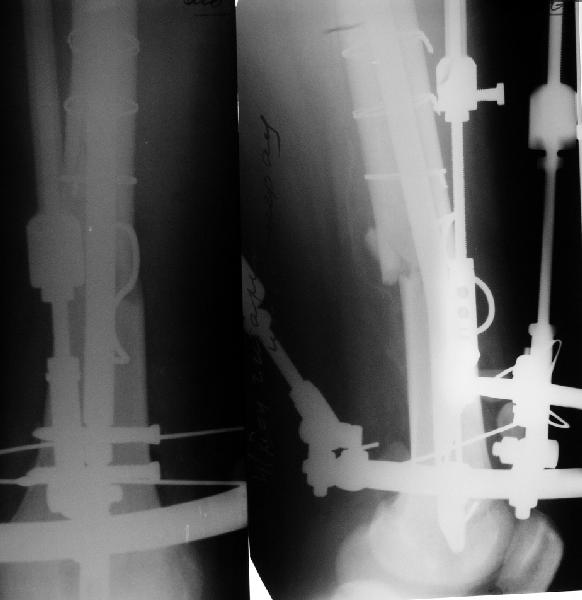

Уважаемые коллеги,пожалуйста, подумайте над следующим ребусом. В нашу клинику поступилпациент из области, 17лет, получивший травму в ДТП 25.08.04, открытый перелом бедра, при поступлении наложено скелетное вытяжение.

30.09.04 на операции выявлен вывих бедра и перелом голени на этой же стороне. Остесинтез бедра все же выполнен, и по заживлении раны пациент переведен к нам. Кроме того у пациента нейропатия седалищного нерва на этой же стороне. В нашей клинике планируется наложение аппарата таз-бедро, для постепенного низведения бедра с последующим открытым вправлением, замена фиксатора на запираемый гвоздь и блокируемый остесинтез голени. Вариант с первичным эндопротезированием мы не рассматривали из-за юного возраста пациента. Вопрос с чего начать? Кроме того, сгибание в коленном суставе в настоящее время (95 градусов) затрудняет остеосинтез голени.Стоит-ли менять гвоздь? Или же спилить торчащий конец во время открытого вправления? Может, попробовать все сделать одномоментно? Заранее спасибо.

Просьба простить за длительное молчание, не было фотоаппарата, чтобы перенести рентгенограммы. Больного прооперировали в прошлый четверг, как и предполагали, голень проблем не доставила(настолько, что даже не ввели дистальные винты по ряду причин: срок после травмы, целая малоберцовая, последующая длительная ходьба без нагрузки, да и гвоздь сел плотно). Изначально планировали после удаления фиксатора антеградно завести стержень и утопить конец, но вопрос был исчерпан, когда выяснилось, что все имеющиеся стержни слишком длинные, пришлось ретроградно забить большеберцовый гвоздь, после рассверливания; серьезные проблемы возникли с устранением ротации. В вертельной области сломали стержень-джойстик(привет установщику эндопротеза), дальнейшие манипуляции проводили пучком спиц и стержнем с кондуктором. Закончили все аппаратом таз-бедро. Решили что возможные огрехи с ротацией устраним после открытого вправления. Снимки прилагаю. Спасибо за участие в обсуждении. Обязуюсь информировать о дальнейших этапах лечения.